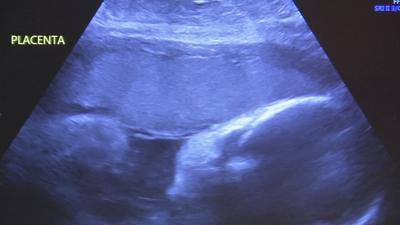

All week long, UofL Health is hosting a series of events targeted at helping women of color feel more comfortable seeking medical care during pregnancy.

According to the CDC, Black, American Indian, and Alaska Native women are two to three times more likely to die from pregnancy-related causes than white women.